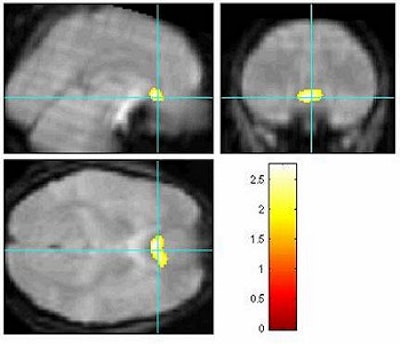

When a study subject was covering up the truth, the anterior cingulate (above) and limbic lobe (below) were two areas in the brain that became active. Images courtesy of Dr. Scott Faro.

An event-related MR design was used for collecting the functional MR images. As expected, the polygraph picked up the liars, Faro said. But the fMRI scans showed significant differences in activation patterns when subjects were lying. Results showed the anterior cingulate, limbic lobe, and inferior frontal regions to be active during the deception process. However, when telling the truth, activation was predominantly seen in the temporal lobe and lentiform nuclei regions.

"We theorized that there are two major processes unique to truth and deception," Faro said. "One process has to do with judgment, planning, and inhibition, and the regions involved are the anterior cingulate, the dorsolateral prefrontal cortex, and the inferior frontal region. You have to judge the question, plan what the answer will be, and inhibit a (true) response," he said.

In contrast, telling the truth should require very little in the way of planning, judgment, or anxiety. This study bore out the theory to some extent, Faro said. One subject had only anterior cingulate activation when lying, while the other liar had both anterior cingulate and amygdala activity, Faro said. The amygdala are involved in fear and anxiety.